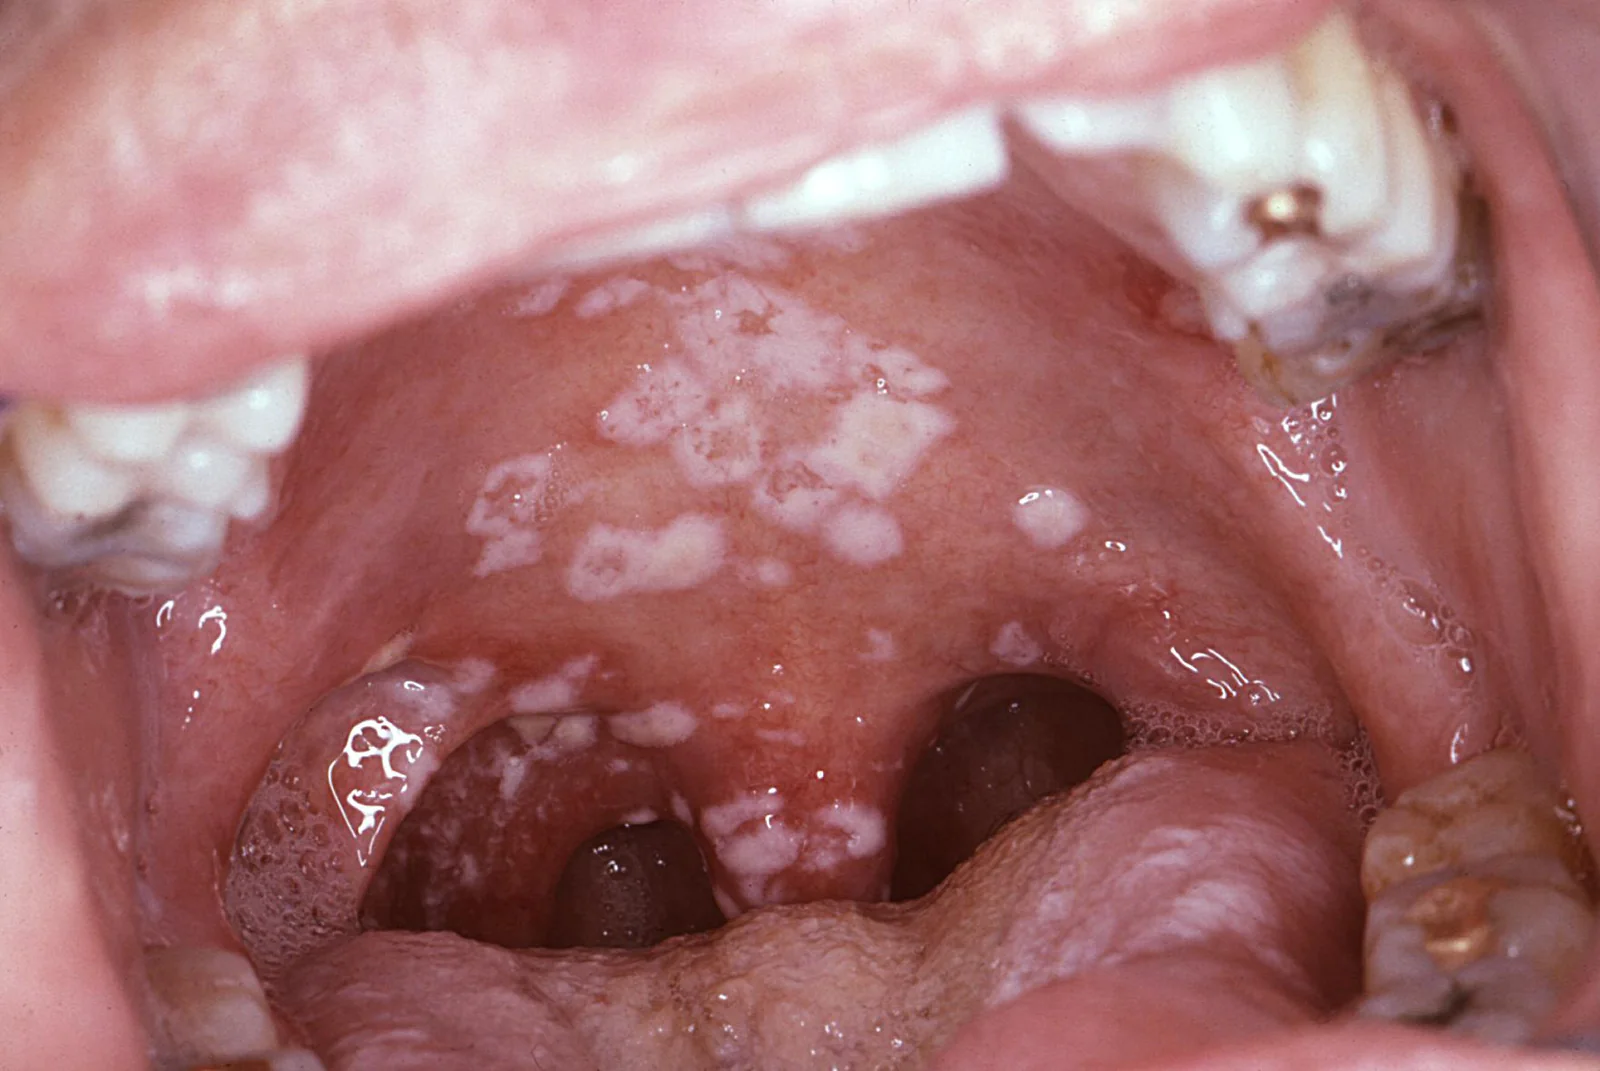

The infection appears as creamy white lesions on the tongue, inner cheeks, roof of the mouth, gums, or tonsils. These patches may look like cottage cheese and can bleed slightly if scraped. While usually mild in healthy people, it can become severe and spread in those with weakened immune systems.

- Creamy white or yellow patches on tongue, inner cheeks, gums, tonsils, or roof of mouth

- Slightly raised lesions with a cottage-cheese appearance

- Mild bleeding if lesions are scraped